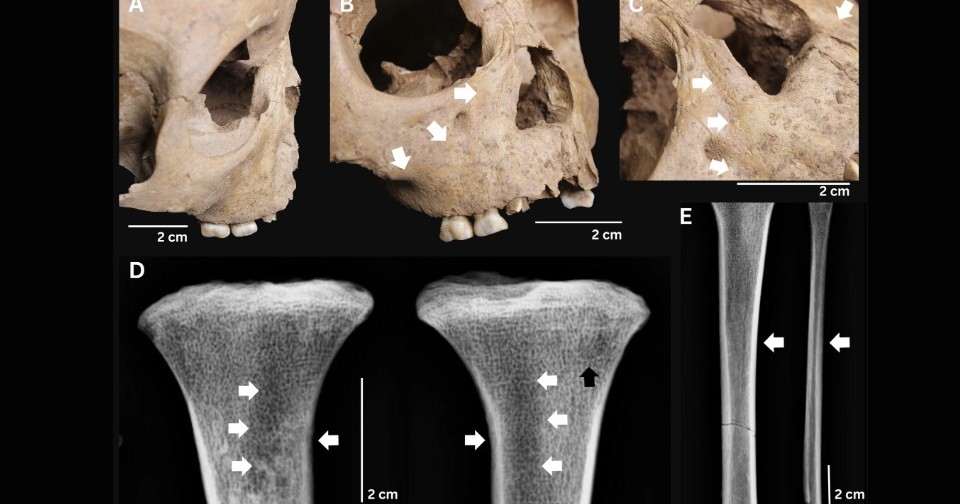

Второй ребенок из памятника Ман-Бак был постарше — он прожил около пяти лет. На его хорошо сохранившемся скелете сначала по фотографиям, а затем и при непосредственном обследовании ученые также выявили признаки аналогичного заболевания: седловидная деформация носа, разрастание костной ткани на отростках верхней челюсти, кортикальное разрастание (гиперостоз) на большеберцовой и малоберцовой кости. Помимо этих потенциальных признаков врожденного трепонематоза, палеопатологи также диагностировали у малыша проявления цинги.